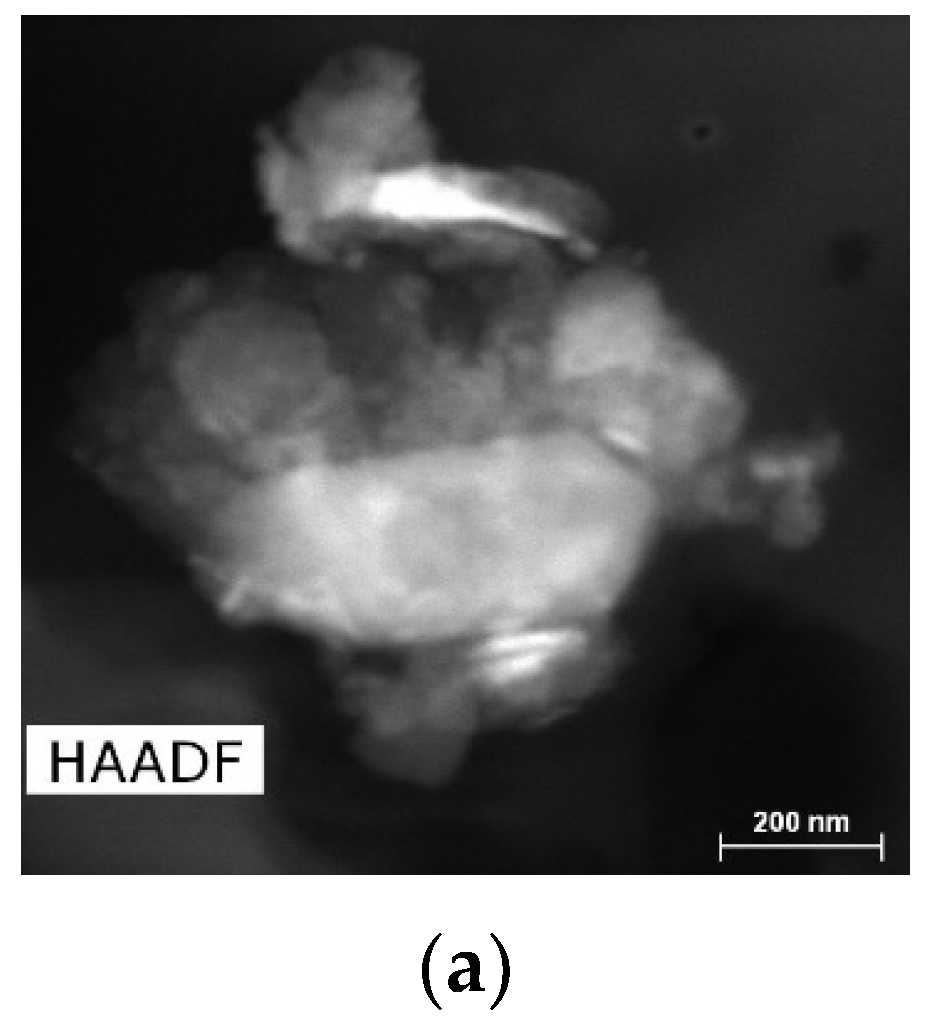

2.1.1. Results of X-ray and Electron Microscopic Studies

4.4. Methods of Scanning Electron Microscopy (SEM) and Transmission Electron Microscopy (TEM) with Energy Dispersive (ED) Analysis